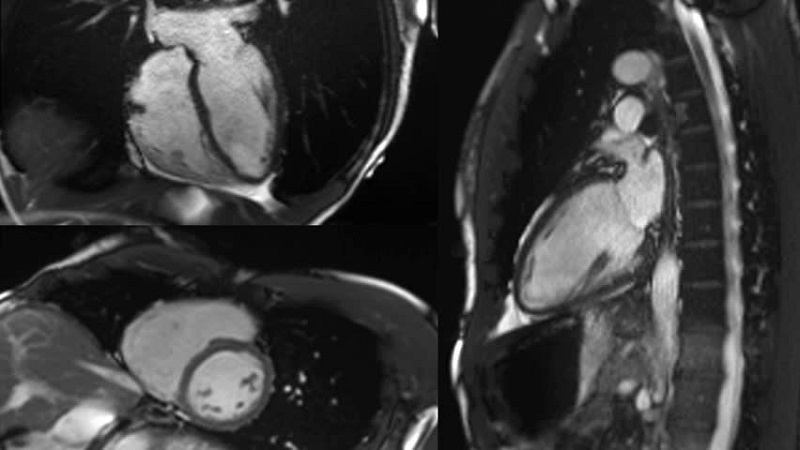

Ba em được bác sĩ chỉ định chụp cộng hưởng từ tim để đánh giá tình trạng cơ tim và mạch máu. Em đang tìm hiểu chi phí chụp cộng hưởng từ tim (1.5 Tesla) tại Bệnh viện Thống Nhất và không biết có được hưởng BHYT không ạ? Mong AloBacsi tư vấn giúp!

Hiện nay, tại Bệnh viện Thống Nhất (TPHCM) có triển khai dịch vụ chụp cộng hưởng từ tim (MRI tim 1.5 Tesla) với mức chi phí như sau: